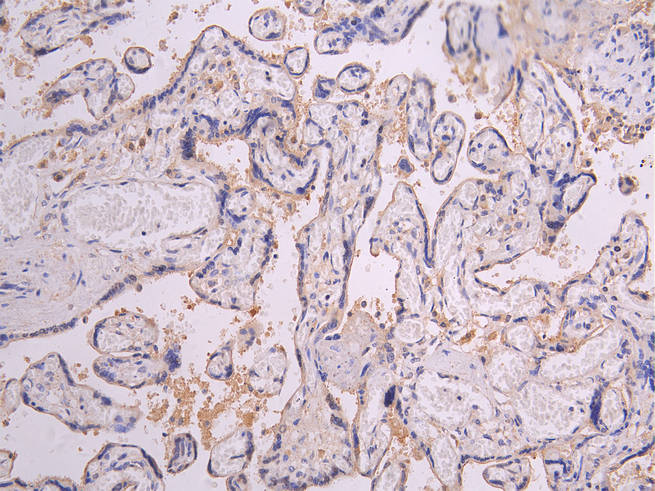

IHC image of CSB-RA018727MA1HU diluted at 1:200 and staining in paraffin-embedded human placenta tissue performed on a Leica BondTM system. After dewaxing and hydration, antigen retrieval was mediated by high pressure in a citrate buffer (pH 6.0). Section was blocked with 10% normal goat serum 30min at RT. Then primary antibody (1% BSA) was incubated at 4°C overnight. The primary is detected by a Goat anti-human polymer IgG labeled by HRP and visualized using 0.05% DAB.

產品描述:CSB-RA018727MA1HU PRLR重組單克隆抗體是針對催乳素受體(Prolactin Receptor)研發的高特異性科研工具。該抗體靶向的PRLR屬于I型細胞因子受體超家族成員,在介導催乳素信號傳導中發揮關鍵作用,參與調控乳腺發育、泌乳功能及生殖系統生理活動。經嚴格驗證,本品在ELISA實驗中可精準識別重組或天然PRLR蛋白,同時在免疫組化(IHC)應用中能清晰顯示組織樣本中PRLR的分布特征,推薦使用稀釋比例為1:50至1:200。適用于體外培養細胞或動物組織切片中PRLR表達水平的定性及定位分析,為研究乳腺生物學、生殖內分泌調控以及相關疾病模型(如乳腺增生或激素依賴性腫瘤機制)提供可靠的檢測支持。其優異的批間穩定性和低交叉反應性保障了實驗結果的重復性與準確性,是基礎科研領域探索PRLR信號通路及功能研究的理想選擇。

推薦稀釋比:Application Recommended Dilution IHC 1:50-1:200